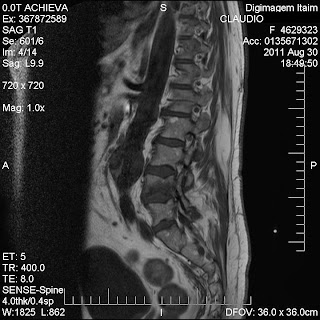

Exame físico, e exames complementares como RX, Ultra-som e Ressonância Magnetica.